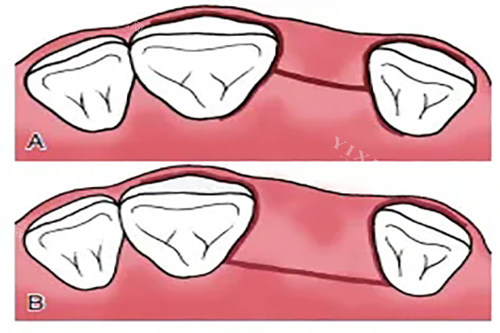

结构设计方面,卡尔斯种植体采用了梅花锁合结构和锥度内连接设计。前者有效增强了种植体的抗旋转能力,后者则提升了基台连接的稳定性。这些设计细节共同作用,使种植体在功能性方面能够满足大多数临床需求。

卡尔斯种植牙特别适合骨条件处于中等水平、预算有限但又希望获得相对长期结果的患者群体。从临床适应症来看,它对牙槽骨高度和密度有一定要求,但不像某些高端种植体那样对骨条件要求极为苛刻。对于存在轻度骨吸收但不愿接受额外植骨手术的患者,卡尔斯可能是一个值得考虑的选择。